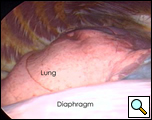

手術室では、全身麻酔と一つの肺換気の下で、胸腔鏡が右中顎線と第7肋間腔に導入された(下のビデオ1)。 嚢胞は、約9x6cmを測定し、右心膜の前外側の側面で容易に視覚化された(図3)。 嚢胞の後方に横隔神経を認めた。 第4肋間腔の前腋窩線に第二の切開を行った。 リングクランプを用いて嚢胞を把握した(図4)。 第5肋間腔の肩甲骨ラインに第三の切開が行われた。 胸腔鏡下はさみと焼灼術(心臓不整脈の可能性を最小限に抑えるために低い設定で)は、心膜から嚢胞を解剖するためにそのポートを介して使用された(図5)。 嚢胞と心膜腔との間の接続が同定された。 それは小さく、はさみで分割されました。 嚢胞の後面の解剖により除去が完了した。 横隔神経は常に明瞭に視覚化されていた。 病理報告では、良性の中皮内嚢胞の診断が確認されました(図6)。

| 図3.:心膜嚢胞の術中所見。 | 図4。 心膜嚢胞のリングクランプ収縮。 |